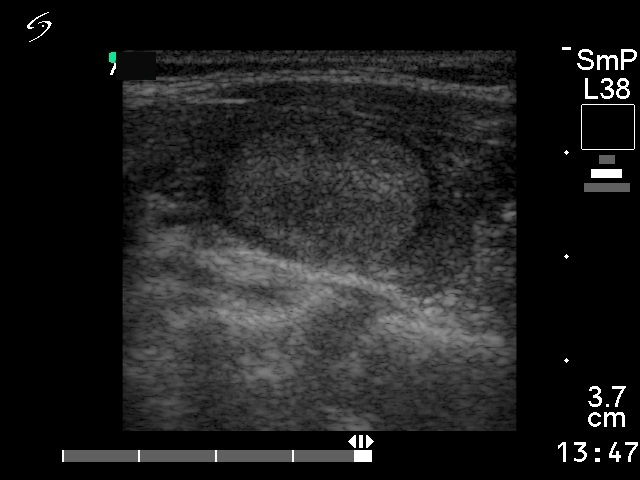

Follicular adenoma - Case 25. |

Ultrasonography: a solitary echonormal nodule within the moderately hypoechogenic left lobe.

Histopathology: microfollicular adenoma and focal lymphocytic thyroiditis.

Comment: in our practice with more than 42,000 FNACs only 5 patients occurred who had carcinoma in an echonormal nodule. Nevertheless, the echo structure of a nodule is influenced by the surrounding normal parenchyma. So, the significance of an echonormal nodule in the case of an underlying Hashimoto thyroiditis (hypoechogenic thyroid) differs from that observed in a patient without thyroiditis, i.e. echonormal thyroid.